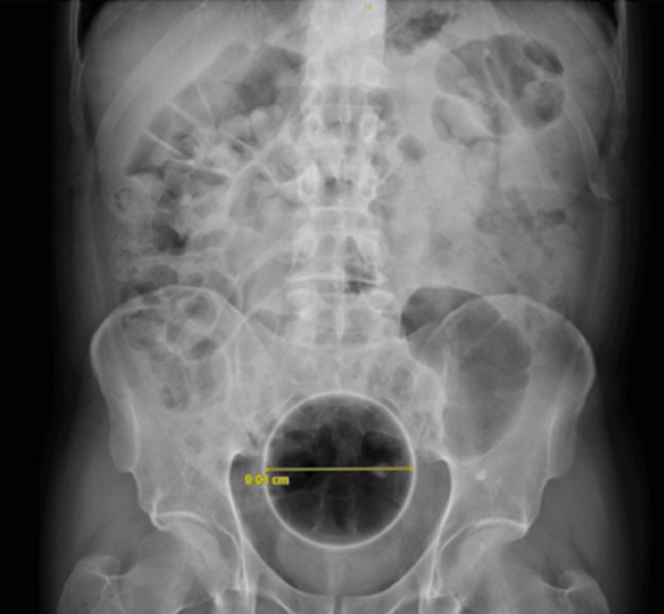

Quelques mois passent. Cette fois, notre homme a introduit dans son rectum une balle en caoutchouc d’environ 9 cm de diamètre, coincée à 6 cm de la marge anale. La radiographie confirme la localisation. Le bloc opératoire rouvre ses portes et la main du chirurgien fait ce qu’elle sait faire. L’histoire se termine à nouveau sans complication.

En 2021, dernier épisode connu : une balle souple en plastique d’environ 10 cm, visualisée à l’imagerie, est extraite, toujours par voie transanale. Il faudra cependant la dégonfler pour qu’elle accepte de faire le chemin inverse, dans un scénario désormais bien rodé.

Ce qui rend ce cas particulièrement intéressant, ce n’est pas seulement la nature des objets – la littérature en regorge, parfois bien plus inattendus encore – mais leur progression en taille. Cinq, puis neuf, puis dix centimètres : entre le premier et le dernier épisode, le diamètre du corps étranger intra-rectal a quasiment doublé.